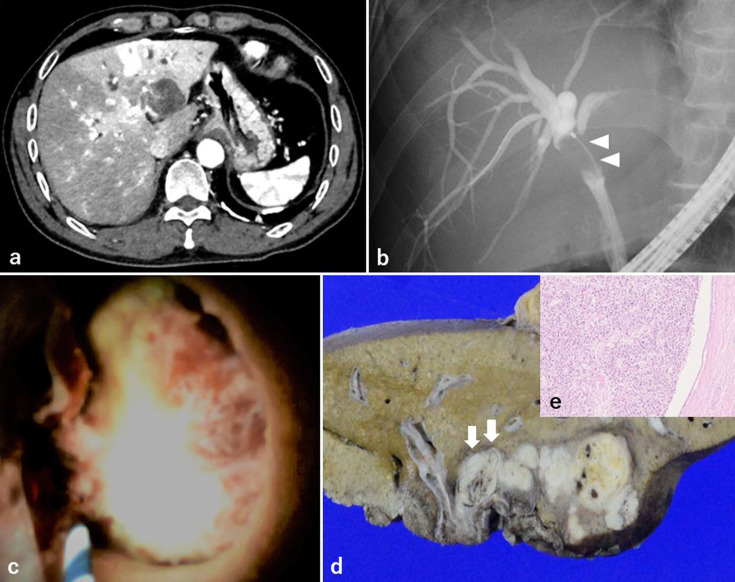

Objective: Bile duct tumor thrombosis in hepatocellular carcinoma (HCC) is a relatively rare event with a poor prognosis. Furthermore, bile duct tumor thrombus in HCC may be misdiagnosed when only imaging modalities are used. The efficiency of peroral cholangioscopy (POCS) in evaluating bile duct lesions has been reported. Patients: We present three cases of HCC with bile duct strictures in which POCS was performed as a preoperative evaluation. Results: In these three cases, diagnosing whether the lesion was a bile duct tumor thrombus on CT and endoscopic retrograde cholangiopancreatography was difficult. We performed POCS in three cases and were able to diagnose the presence of bile duct tumor thrombus of HCC, including differentiation from extrinsic compression of the bile duct. Conclusion: POCS for HCC with bile duct features is useful for the preoperative diagnosis of bile duct tumor thrombus, especially in cases where the surgical procedure depends on the presence of bile duct tumor thrombus.

Abstract Image